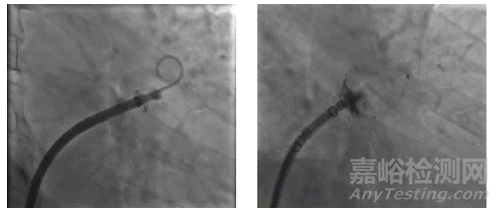

左心耳解剖:DSA 造影顯示心耳為菜花型,口徑 20.11mm,深度 16.8mm,無(wú)明顯分葉。

2. 手術(shù)操作過(guò)程

器械選擇:選用24mm 規(guī)格 WATCHMAN FLX Pro,考慮到患者需長(zhǎng)期 DAPT,優(yōu)先選擇涂層器械以降低 DRT 風(fēng)險(xiǎn)。

釋放與評(píng)估:術(shù)后DSA 與 TEE 顯示封堵器位置正常,瓣周漏<1mm,無(wú)心包積液。

全球首款,波科涂層左心耳封堵器獲批上市

▲術(shù)前左心耳造影(左);封堵器展開(kāi)后造影(右)

3. 術(shù)后專家反饋

樊友啟教授在術(shù)后表示:“冠脈術(shù)后合并房顫的患者,‘DAPT + 抗凝’的三聯(lián)治療出血風(fēng)險(xiǎn)是單獨(dú) DAPT 的 2-3 倍。WATCHMAN FLX Pro 在中國(guó)上市,標(biāo)志著 LAAC 進(jìn)入涂層時(shí)代 —— 涂層加速內(nèi)皮化后,患者或可從‘三聯(lián)治療’轉(zhuǎn)為‘單純 DAPT’,大幅降低出血風(fēng)險(xiǎn),未來(lái)我們計(jì)劃開(kāi)展相關(guān)臨床研究驗(yàn)證這一方案的可行性。”